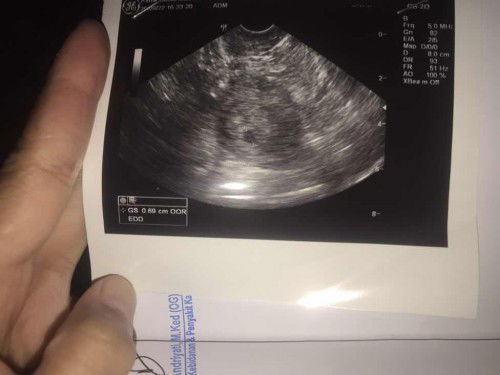

Cek usg transvaginal penampakan seperti ada 2 kantung

Bunda aku usg transvaginal dgn usia kandungan 5w 3d dan hasil nya seperti ini. Aku pas liat di monitor ga kelihatan jelas, udah sampai rumah ternyata di kasih print usg nya. Dan aku lihat di sebelah kiri kantung yg di ukur dokter ada seperti kantung lagi. Itu apa ya bund? Apa kemungkinan kembar atau apaan iya? Aku bingung itu apa, soal nya dokter ga jelasin. Dan sampai rumah baru liat. Mohon tanggapan nya bunda?